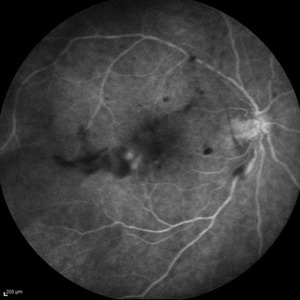

Behcet's Disease Behcet's DiseaseMar 13 2013 by Hamid Ahmadieh, MD Early phase FA of the right eye of a 23-year-old man with retinal vasculitis and branch retinal vein occlusion (BRVO) due to Behcet's disease . Photographer: Solmaz Shahmohammad, Negah Eye Center, Tehran Imaging device: Heidelberg Spectralis Condition/keywords: branch retinal vein occlusion (BRVO), retinal vasculitis

Behcet's Disease Behcet's DiseaseMar 13 2013 by Hamid Ahmadieh, MD Mid phase FA of the right eye of a 23-year-old man with retinal vasculitis and branch retinal vein occlusion (BRVO) due to Behcet's disease . Photographer: Solmaz Shahmohammad, Negah Eye Center, Tehran Imaging device: Heidelberg Spectralis Condition/keywords: branch retinal vein occlusion (BRVO), retinal vasculitis